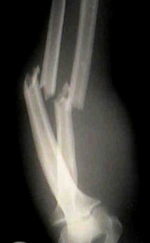

Descriptio roentgenogrammatum cum schemate

На рентгенограмі – перелом кісток лівого передпліччя в н/3 зі зміщенням уламків.

Мал.1.

Рентгенограма кісток предпліччя при переломі обох кісток предпліччя (пряма проекція).

Мал. 2.

Рентгенограма кісток предпліччя при переломі обох кісток предпліччя (бокова проекція).

Рентгенограма кісток предпліччя при переломі обох кісток предпліччя (пряма і бокова проекція).